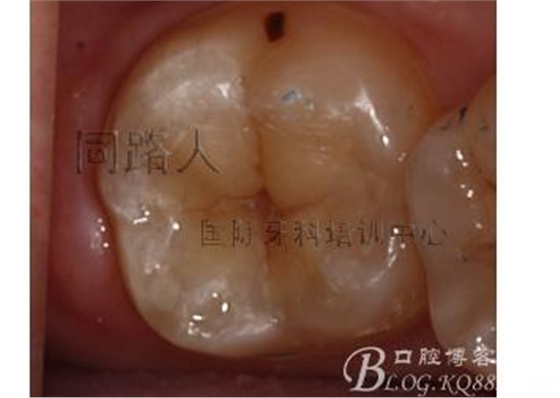

有的同行要看口內照片,意思是你做得再怎么好,也得在口內粘結完效果好才行

嵌體的粘結很簡單,在此我推薦初學者用雙固化樹脂水門汀進行粘接,熟練以后再研究樹脂粘接。對牙本質封閉的牙體進行全酸,對從模型上摳下來的樹脂嵌體噴砂,然后往牙體和修復體表面摩擦法涂粘結劑,用氣槍充分吹15秒,然后打上樹脂水門汀,嵌體就位。去除多余的水門汀,點照射固定。等待五分鐘的化學聚合,然后強光照射,涂擦阻聚劑,再次強光照射!調合,拋光